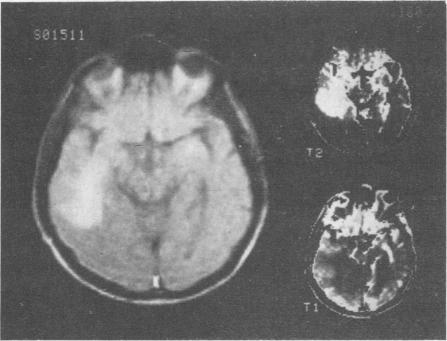

Nuclear magnetic resonance imaging can produce tomographic images of the body without ionizing radiation. Images of the head, chest, abdomen, pelvis and extremities have been obtained and normal structures and pathology have been identified. Soft tissue contrast with this method is superior to that with x-ray computerized tomography and its spatial resolution is approaching that of x-ray computerized tomography. In addition, nuclear magnetic resonance imaging enables us to image along the sagittal and coronal planes directly, and it does not produce obscuring artifacts by bone.

核磁共振成像能够在不使用电离辐射的情况下生成人体断层图像。已经获得了头部、胸部、腹部、骨盆和四肢的图像,并识别出了正常结构和病变。这种方法的软组织对比度优于X射线计算机断层扫描,其空间分辨率正在接近X射线计算机断层扫描。此外,核磁共振成像使我们能够直接沿矢状面和冠状面成像,并且不会产生由骨骼引起的模糊伪影。